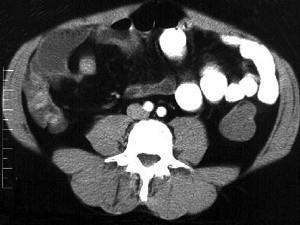

问题 女,30岁,右下腹痛,腹泻便秘交替出现,消瘦乏力,血沉加快,X线检查如图,最佳的诊断是 ( )

选项 A.小肠癌 B.小肠结核 C.小肠克罗恩病 D.结肠癌 E.阑尾炎

答案 C